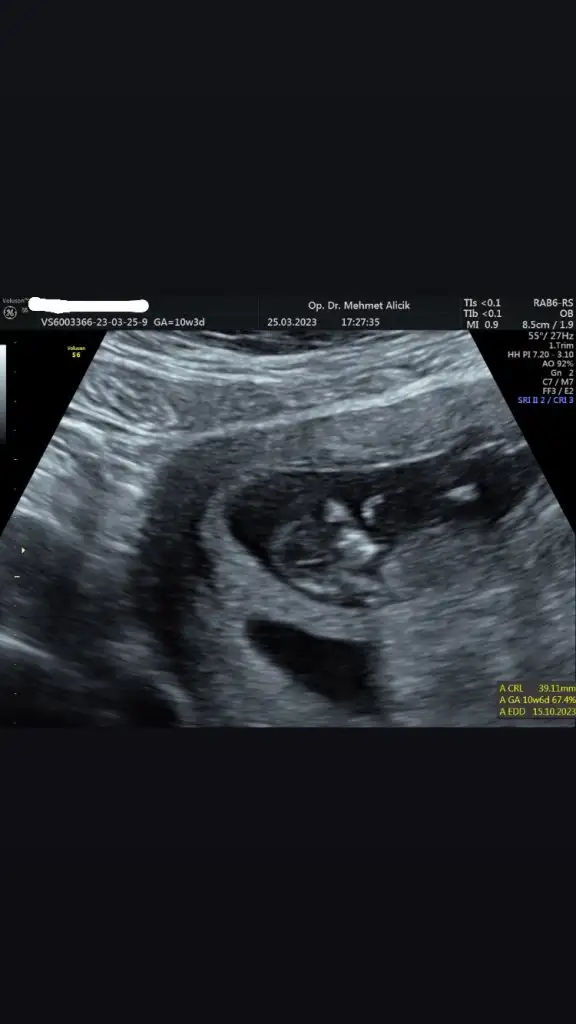

Merhaba 11+4 olduk bugün 🙏🏻 aranızda ultrason görüntüsünden cinsiyet anlayan var mı acaba ☺️ ultrasonda bakarken kafası böyle değildi daha yuvarlaktı ama bilemiyorum ben bakınca erkek diyorum ama içimden kız geçiyor 🥰

Papatyamaviss Papatyamaviss benim de mi belli olmaz.. ekledim en uygun foto bu 10.hafta bugüne ait